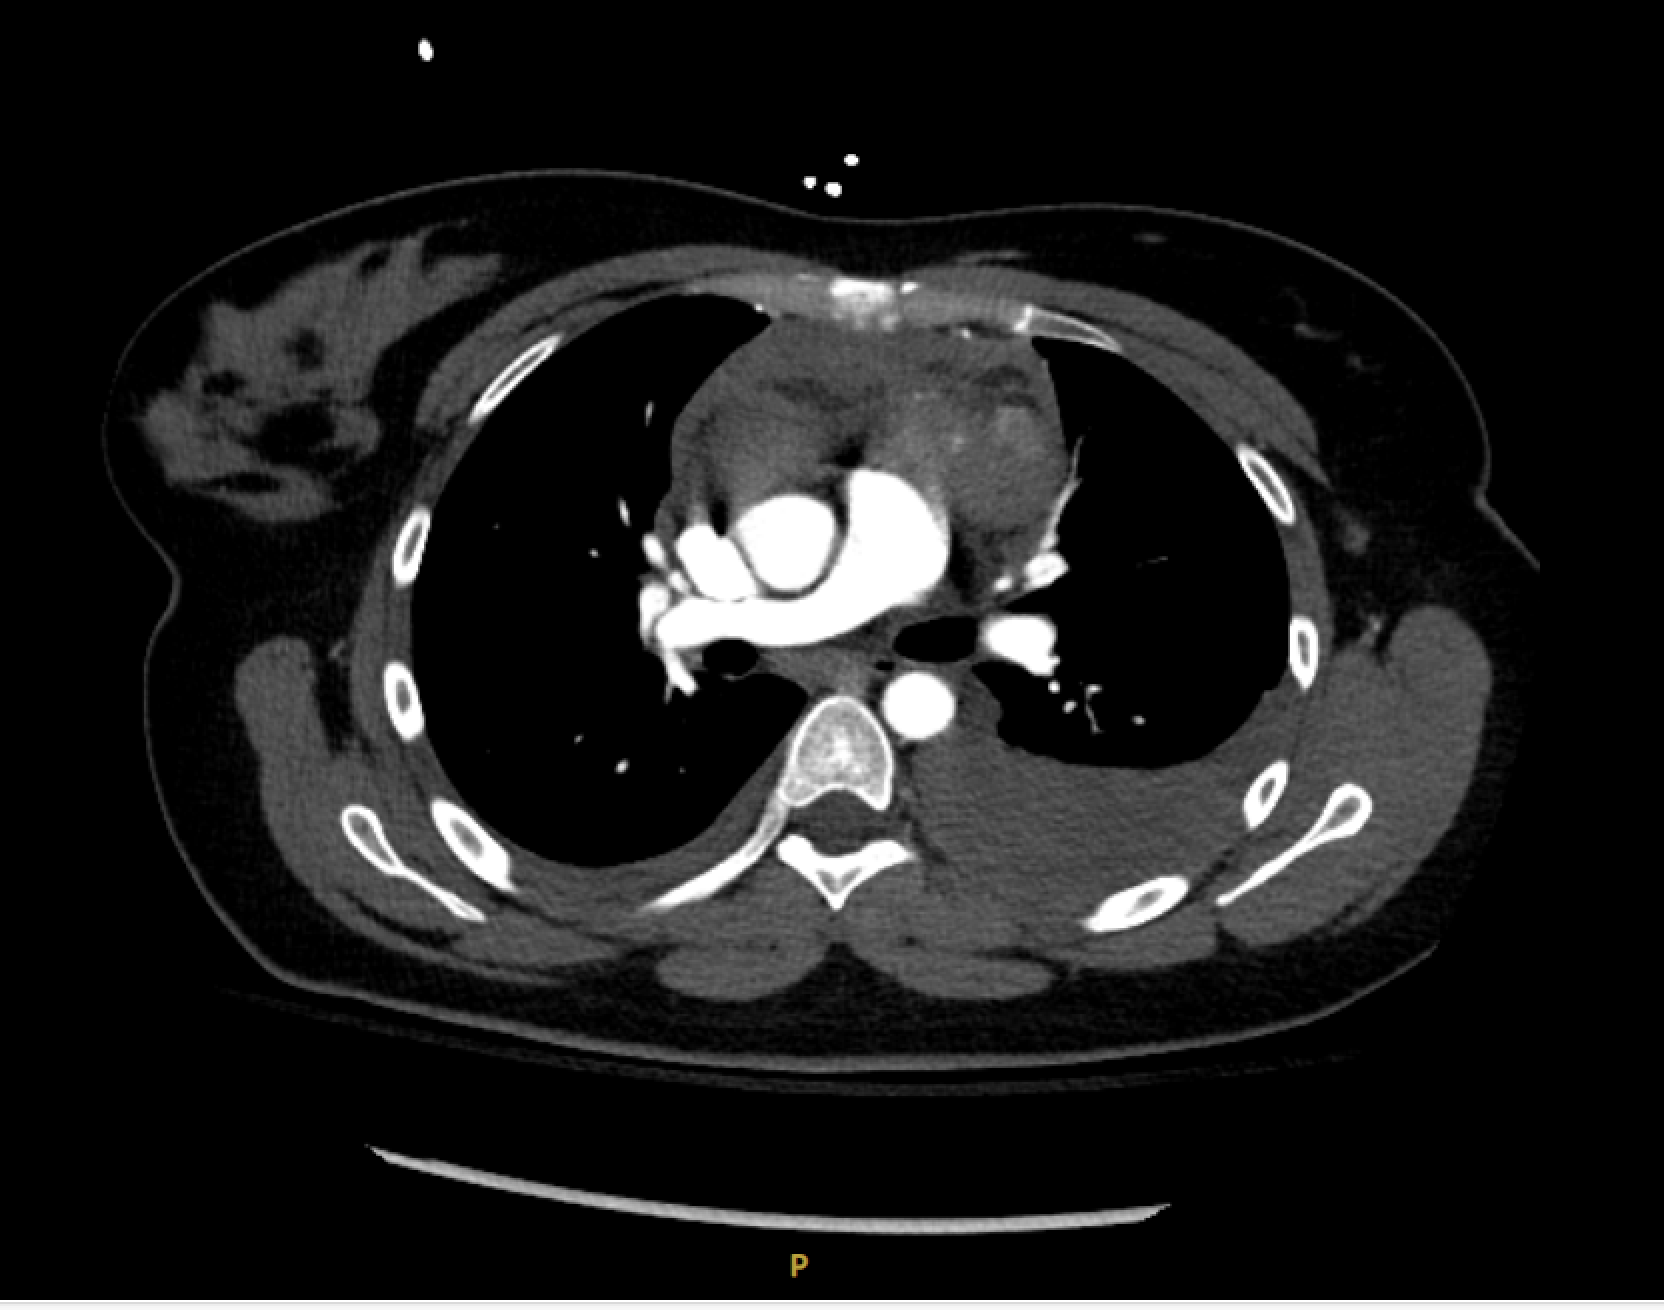

Case Presentation: The patient is a 32-year-old female who presented with a five week history of chest pain that radiated to the left shoulder and back with associated chest wall bruising that resolved prior to presentation. Pain was 7/10 in intensity, worsened with deep inspiration, positional, and associated with mild dyspnea. Medical history includes rheumatoid arthritis, and preeclampsia. On presentation, vital signs were normal, and physical exam was unremarkable. Troponin trend was negative and EKG with normal sinus rhythm. Calcium was elevated to 11.1 mg/dL. Computed tomography (CT) angiography of the chest showed a moderate to large anterior mediastinal hematoma with suspected left sided mass with blush, consistent with active extravasation (Image 1). It also showed hemorrhagic bilateral pleural effusions and a small pericardial effusion. The aorta and thoracic arterial vasculature were unremarkable. She denied anticoagulation and NSAID use. The patient was initially hemodynamically stable, so cardiothoracic surgery opted for conservative management in the ICU with chest tube placement for the left hemothorax. Magnetic resonance imaging of the chest with contrast confirmed an anterior mediastinal mass 3.2cm in size. There was no evidence of metastatic disease on CT abdomen and pelvis. Tumor markers lactate dehydrogenase, alpha-fetoprotein, beta-human chorionic gonadotropin were within normal limits.Subsequently, her hemoglobin dropped from 13 g/dL to 7.3 g/dL with symptomatic fatigue and tachycardia. Patient underwent a median sternotomy with resection of the mediastinal mass. Operative findings included an extensive hematoma ventral to the main pulmonary trunk that dissected through mediastinal fat and thymic tissue. Pathology revealed a 4 cm intrathymic parathyroid adenoma, associated with a large organizing hematoma and fibrosis (22 x 11 x 4 cm, Image 2).Patient recovered without complications.